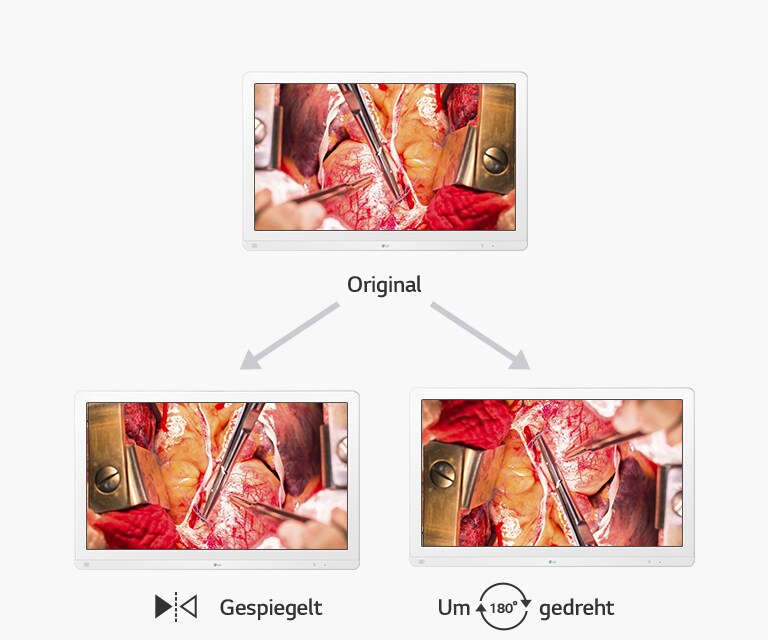

Der OP-Monitor 32HL714S unterstützt 115% sRGB (Farbraum) und über 99% sRGB (Farbabdeckung) sowie den Standard DICOM Part 14 und wurde für eine genaue Farberkennung und Tiefenwahrnehmung während chirurgischer Eingriffe entwickelt. So können Chirurgen genaue, realitätsgetreue Bilder betrachten und Operationen präzise durchführen.